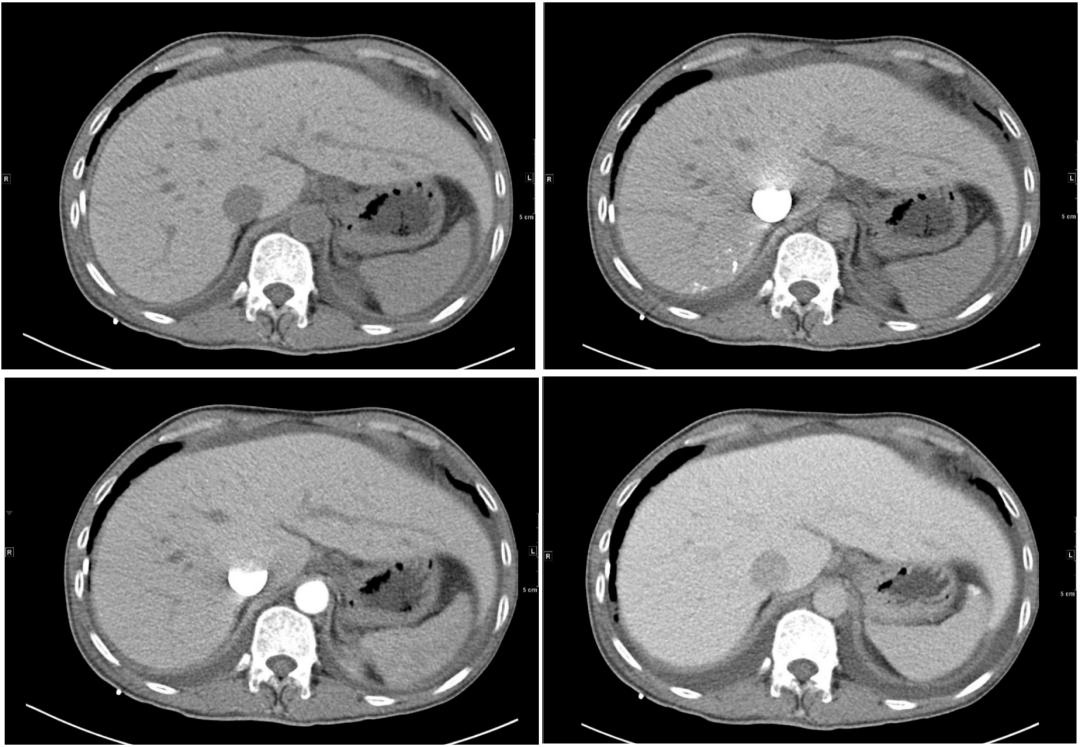

我们再来看第2个病例:46岁男性患者,因低血压、全身可凹性水肿、劳力性呼吸困难。行腹盆增强CT检查,检查图像如下:

我们再看一下肝脏层面增强CT图像(依次是平扫、动脉期、门脉期、延迟期):

患者的影像学,需要我们影像及临床大夫仔细考虑的就是:肝脏体积增大、密度弥漫性增高。

肝脏体积增大、密度弥漫性增高,主要考虑血色病(遗传性血色素沉着病、继发性含铁血黄素沉着症)、糖原沉积症(GSD)、肝豆状核变性(Wilson病)、胺碘酮治疗后改变四种疾病。

结合影像学及实验室辅助检查可确诊:该患者是血色病患者。

患者没有做心肌MRI,基因分析等检查,无法明确鉴别是原发性还是继发血色病,但一些典型特征:皮肤特征性发黑、无外源内源铁的异常沉积病史、CT显示脾脏密度正常、超声提示心肌病变,血检正常、心肌酶谱NT-proBNP异常,可以推断很大可能属于原发性血色病。